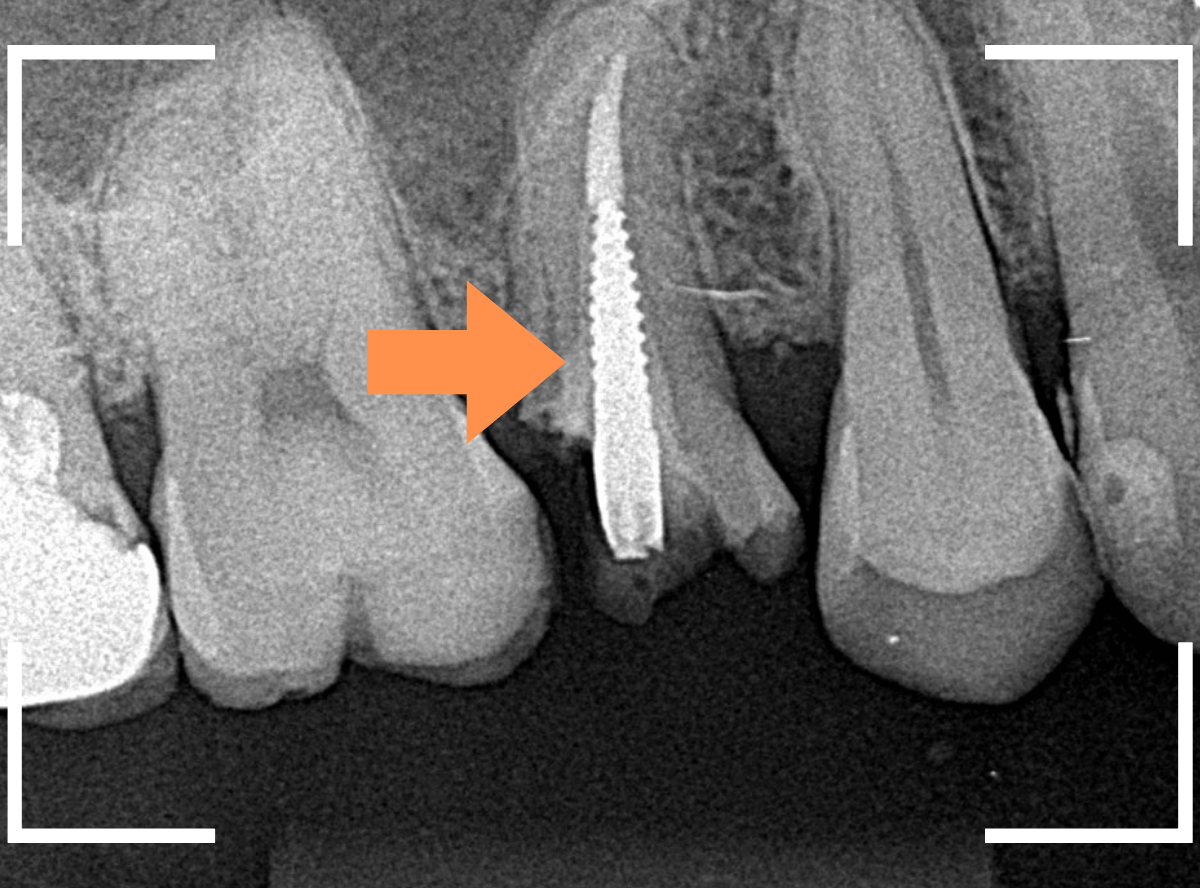

Case.2

欠けてしまった歯を、土台から再治療

つめものごと、歯が欠けてしまったという患者さんのケースです。

歯全体が欠けてしまっていますので、今回はさし歯(クラウン)で治療をする必要がある旨ご説明したところ、(オール)ジルコニア・クラウンでの治療を選ばれました。

まずは、レントゲン写真で歯の内部を確認します。

幸い歯が欠けたのは表面のみで済んでいましたが、矢印の歯の土台(コア)からしっかり作り直したいのですが、細い歯に金属ピンの部分が歯の根までしっかり入っているので、これを外すのはかなり大変そうです(><)

一番懸念されるのは、金属ピンを外す時に歯が割れてしまう事です。

あまりに危険な際は無理に外そうとせずに、そのままさし歯だけ作り直す方が良い事もあるのですが、今回は患者さんの同意を得て、金属を外してコアを作り直す事にしました。

歯を傷つけないように、専用の超音波チップの振動を使って、30分ほどかけて金属ピンを何とか外せました。